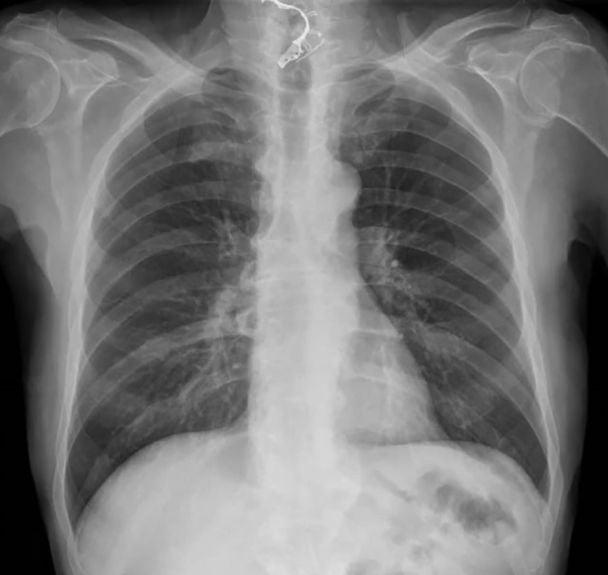

Лікарі не були впевнені, що заважає пенсіонеру їсти, але помітили, що він не має верхнього ряду вставних зубів. Потім рентген підтвердив причину проблеми. Протези застрягли у нижній шийній області.

Чоловік проковтнув зубні протези / Фото: Jam Press

Після операції було зроблено ще один рентген, який не показав жодних ознак перфорації стравоходу.